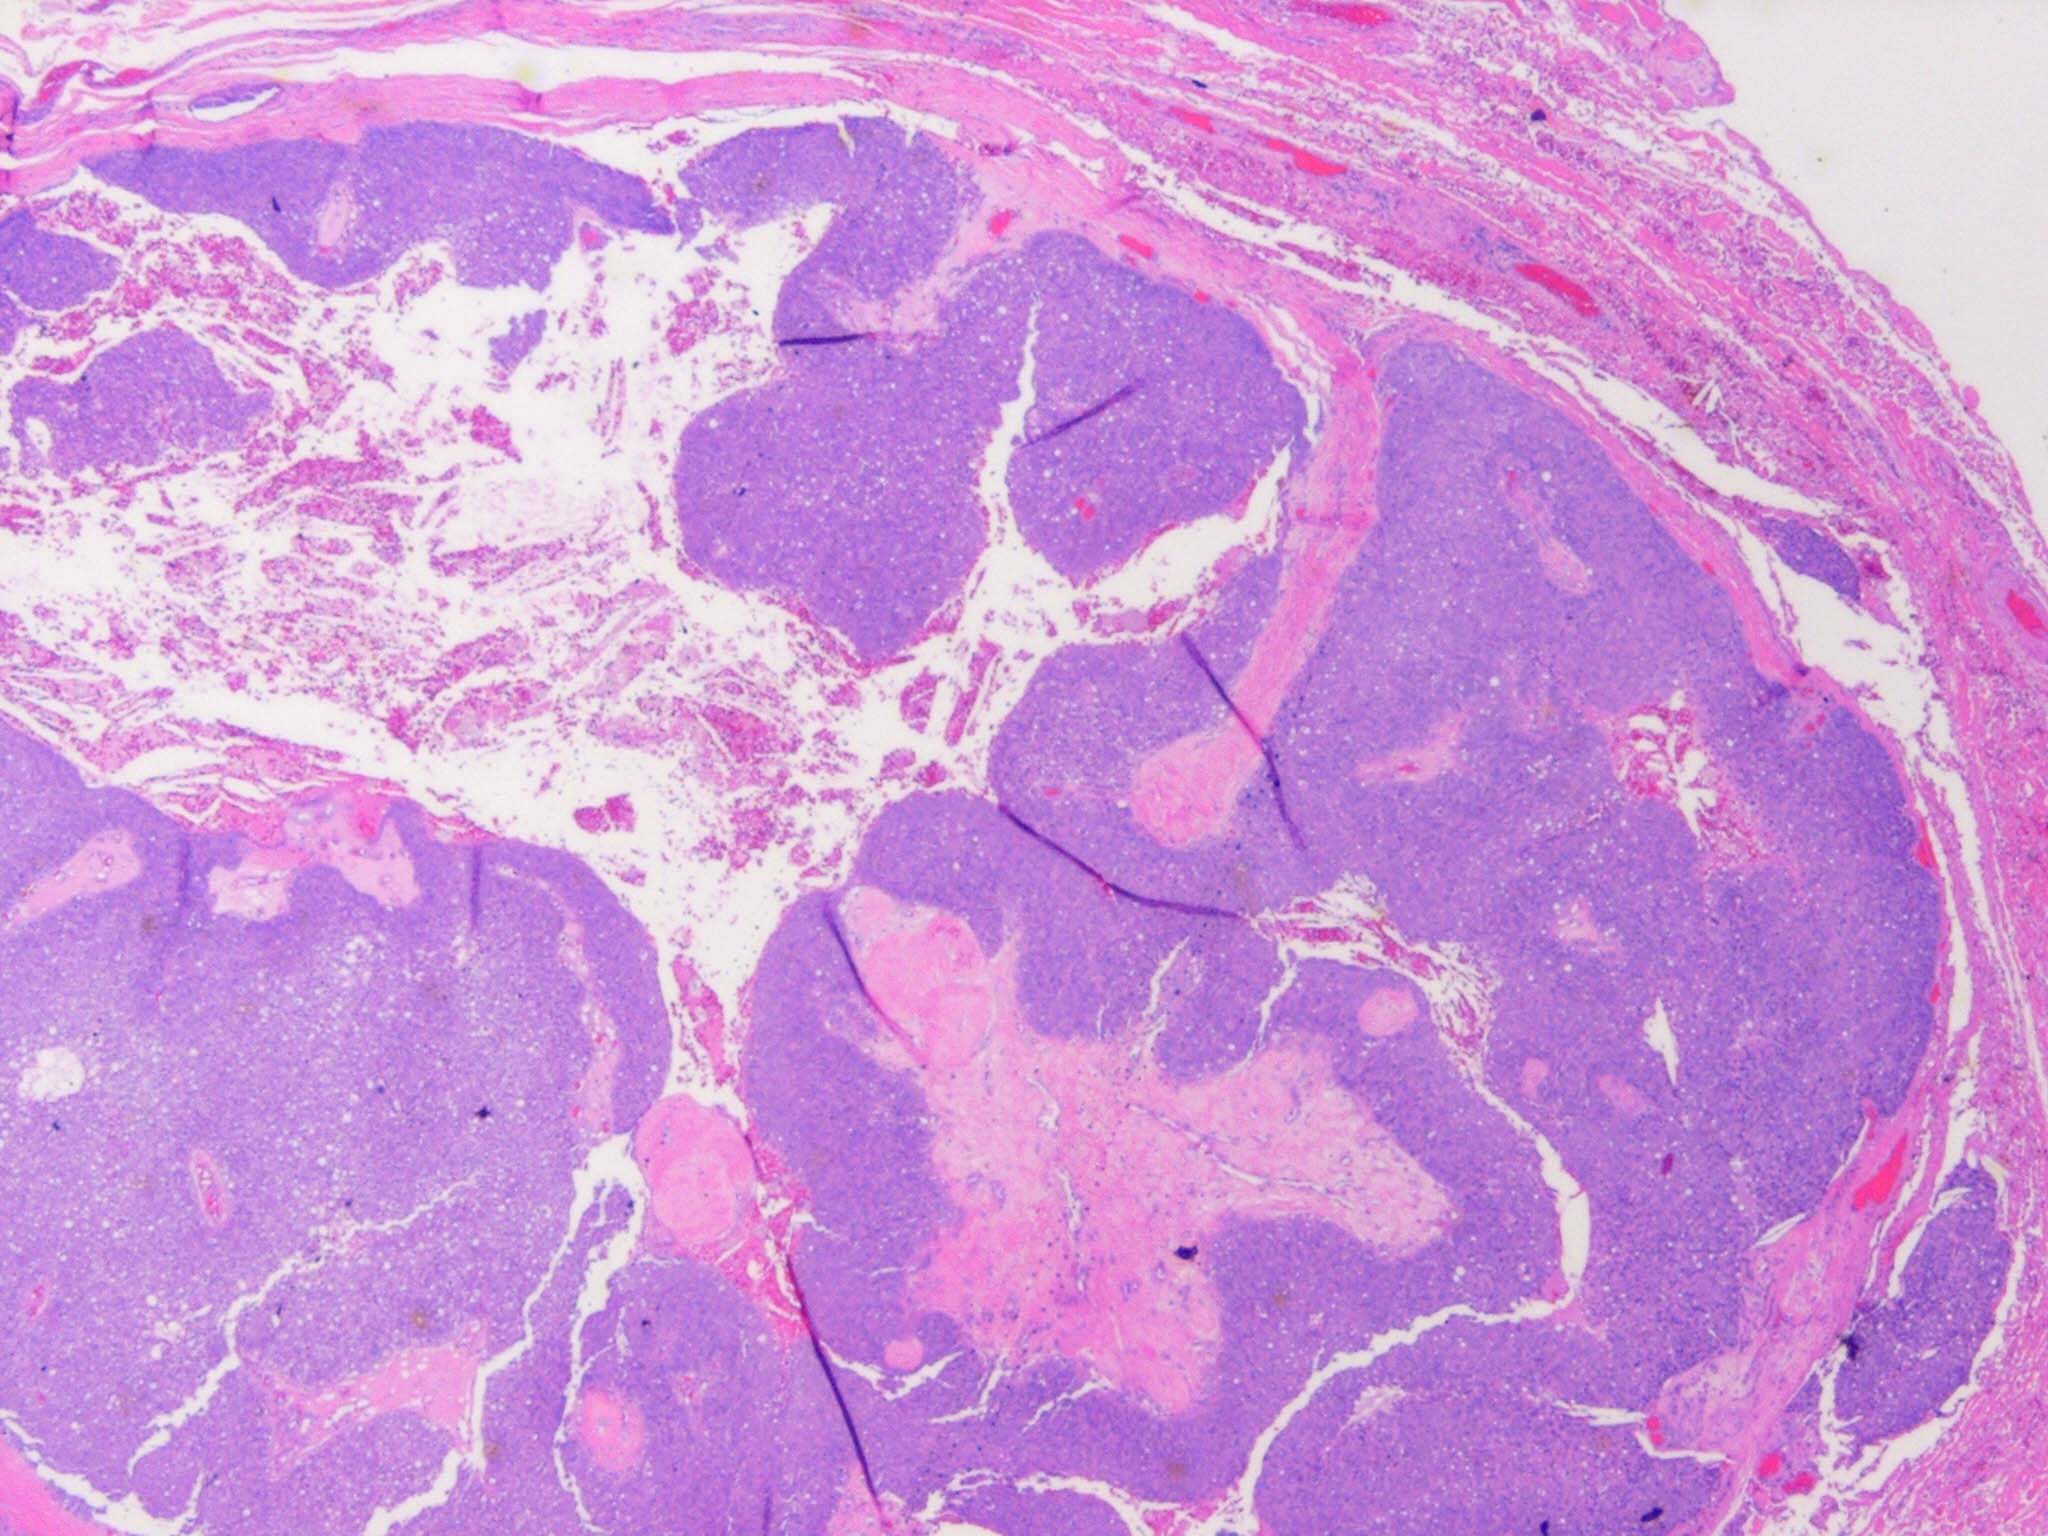

Sebaceous carcinoma = الكارسينوما الدهنية